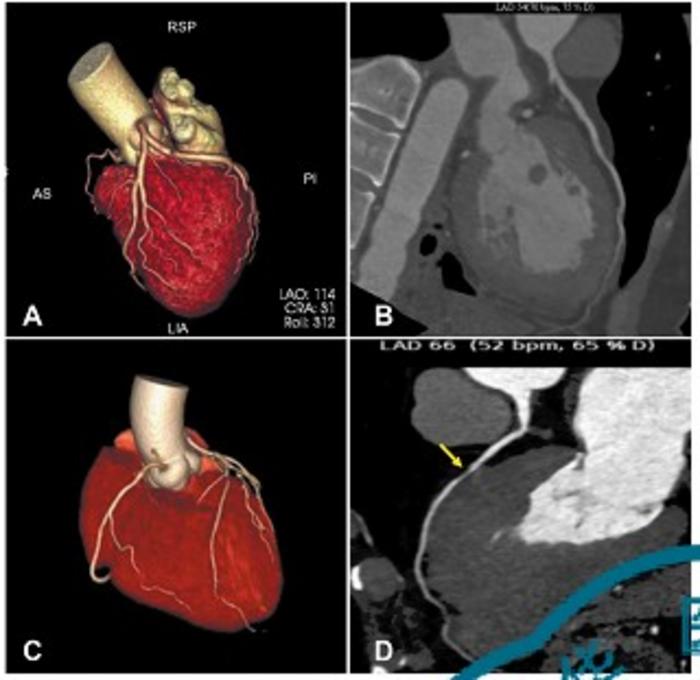

Patients experiencing acute pulmonary embolism without and with pre-existing coronary artery stenosis

Patients without pre-existing coronary artery stenosis (A, B) are at higher risk of adverse effects from acute pulmonary embolism than patients with CAS (C, D). These adverse effects include right ventricular dysfunction, elevated heart rate and elevated pulmonary artery pressure.

Credit: Zhi-Cheng Jing in Chinese Medical Journal Image Source Link: https://journals.lww.com/cmj/fulltext/2025/08200/coronary_artery_stenosis_associated_with_right.13.aspx